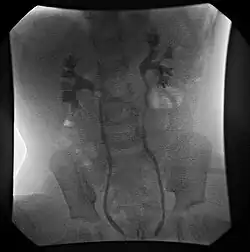

![]() | |

| Ultrasound image showing abnormal vesicoureteral junction and dilated distal ureter resulting in primary vesicoureteral reflux (VUR). | |

Vesicoureteral reflux (VUR), also known as vesicoureteric reflux, is a condition in which urine flows retrograde, or backward, from the bladder into one or both ureters and then to the renal calyx or kidneys.[1][2] Urine normally travels in one direction (forward, or anterograde) from the kidneys to the bladder via the ureters, with a one-way valve at the vesicoureteral (ureteral-bladder) junction preventing backflow. The valve is formed by oblique tunneling of the distal ureter through the wall of the bladder, creating a short length of ureter (1–2 cm) that can be compressed as the bladder fills. Reflux occurs if the ureter enters the bladder without sufficient tunneling, i.e., too "end-on".

Primary VUR

Insufficient submucosal length of the ureter relative to its diameter causes inadequacy of the valvular mechanism. This is precipitated by a congenital defect or lack of longitudinal muscle of the portion of the ureter within the bladder resulting in an ureterovesicular junction (UVJ) abnormality.